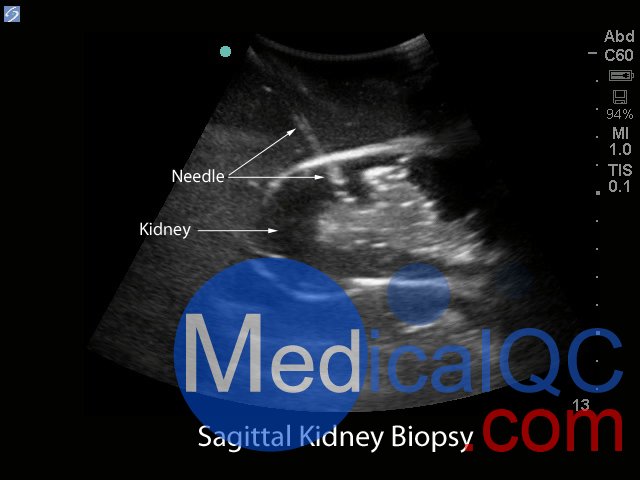

BPRB-2011腎活檢超聲訓(xùn)練模型,BPRB-2011腎活檢模體非常適合協(xié)助臨床醫(yī)生熟練使用超聲指導(dǎo)經(jīng)皮腎臟活檢程序。使用我們極其現(xiàn)實(shí)和持久的超聲培訓(xùn)模型,獲得超聲引導(dǎo)的腎活檢程序的能力和能力。

Blue Phantom的經(jīng)皮腎穿刺活檢超聲訓(xùn)練模型允許使用芯針穿刺活檢或穿刺穿刺技術(shù)重復(fù)進(jìn)行針頭活檢。該模型提供了解剖學(xué)上正確的成年男性軀干,其超聲組織模塊包含皮膚,肋骨和右腎以及周圍組織。腎臟的內(nèi)部和外部結(jié)構(gòu)在其逼真度和成像特性方面極佳,并且包含腎皮質(zhì),腎髓質(zhì)以及主要和次要的花萼。使用與真實(shí)人體組織的聲學(xué)特征相匹配的Blue Phantom模擬組織構(gòu)造而成,因此,當(dāng)您在我們的訓(xùn)練模型上使用超聲系統(tǒng)時(shí),您將獲得與在臨床環(huán)境中對(duì)患者進(jìn)行成像所期望的相同質(zhì)量。

超聲成像和程序技能包括;使用超聲系統(tǒng)控制,換能器定位和移動(dòng),識(shí)別腎解剖結(jié)構(gòu),在腎活檢期間避免肋骨出現(xiàn),避免肋骨出現(xiàn),使用超聲將目標(biāo)對(duì)準(zhǔn)腎活檢的適當(dāng)位置并執(zhí)行超聲引導(dǎo)的腎活檢程序。使用配置了適當(dāng)?shù)哪I臟活檢換能器的任何超聲成像系統(tǒng),此超聲動(dòng)手訓(xùn)練模型將表現(xiàn)良好。這種超聲體模模型非常適合包括腎臟科,介入放射學(xué),外科手術(shù),外科手術(shù)訓(xùn)練計(jì)劃,超聲訓(xùn)練計(jì)劃,模擬中心,外科技能中心,醫(yī)學(xué)教育設(shè)施,腎臟活檢設(shè)備制造商和超聲制造商進(jìn)行超聲教育和演示的專業(yè)。